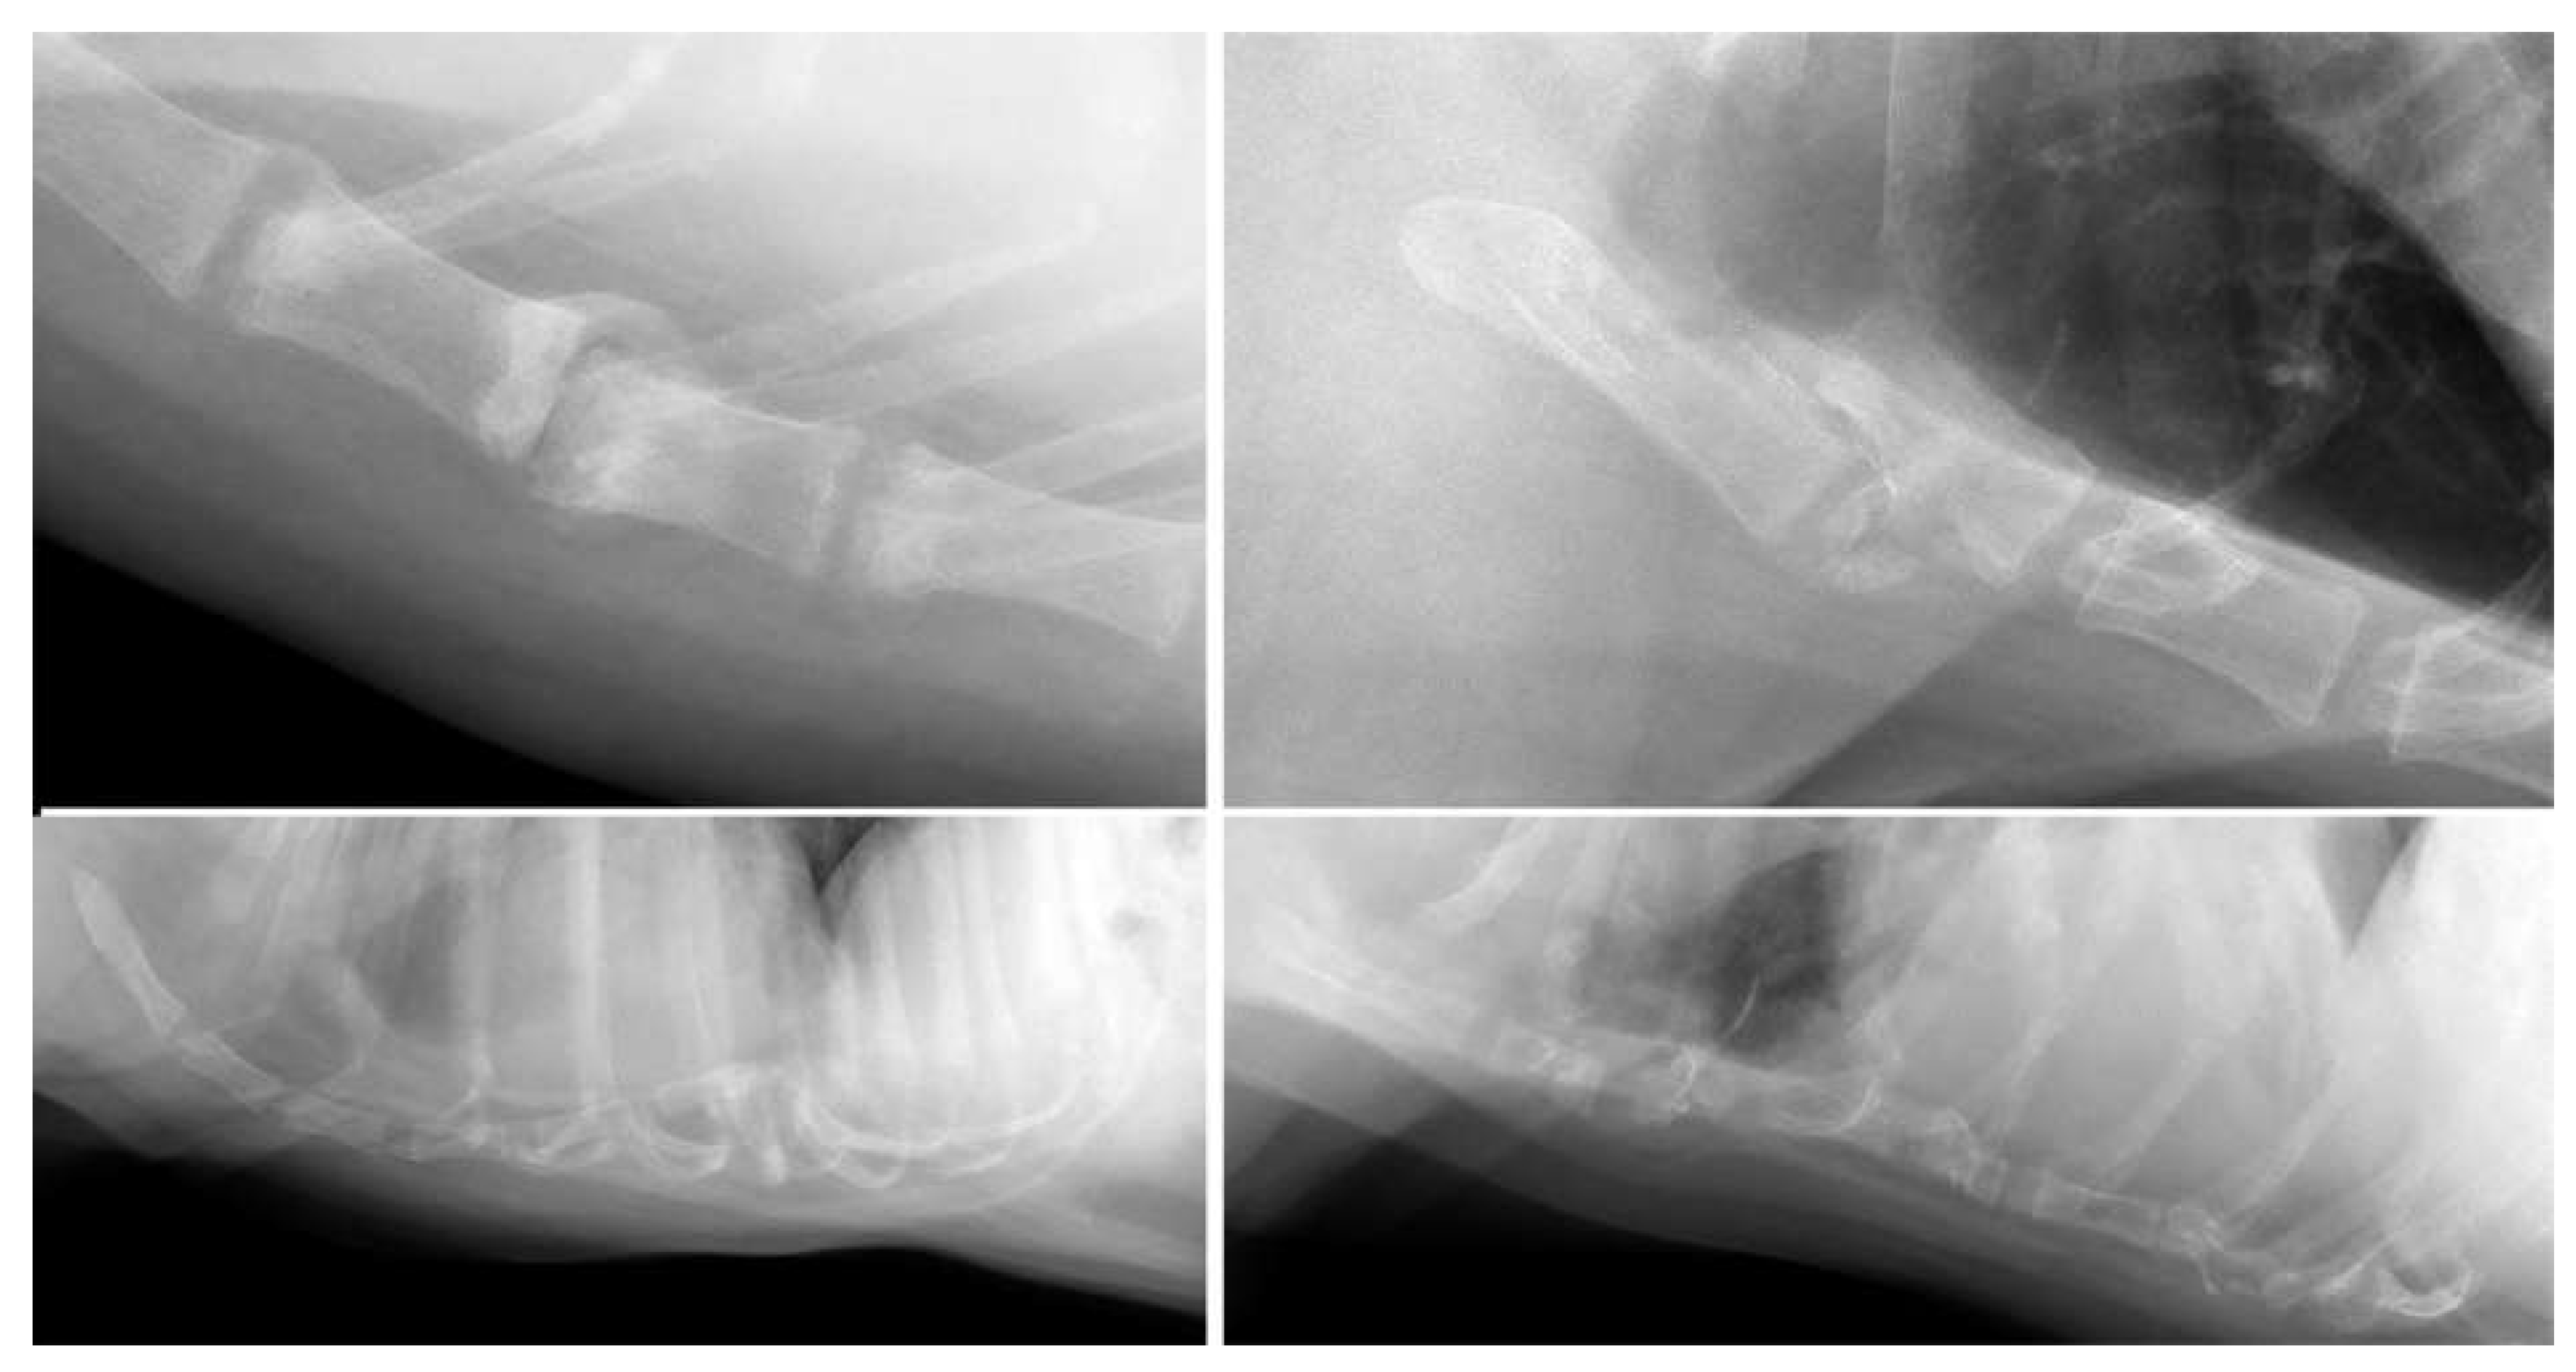

| Post-trauma (n = 12) | Dislocation (n = 5); collapse (n = 8); fracture (n = 2) | Labrador Retriever (3/62); mixed (2/145); Alaskan Malamute (1/4); Boxer (1/13); Chihuahua (1/28); Chow Chow (1/3); German Shepherd (1/21); Labradoodle (1/22); Welsh Springer Spaniel (1/3) |